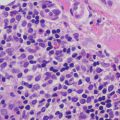

3.5.2 Histology

AGEP is uncommon in children, but when it occurs, shows the same histologic changes as have been reported in adults [35]. Subcorneal pustules comprised of neutrophils are present within a slightly spongiotic epidermis (Fig. 3.12). Parakeratosis is infrequent, except in older lesions. The granular layer persists and acanthosis is not a common finding. Within the dermis, there is a mixed inflammatory infiltrate that consists of neutrophils, eosinophils, and histiocytes [36] (Fig. 3.13).

Fig. 3.12

AGEP demonstrates subcorneal and intraepidermal neutrophilic abscesses. There is focal spongiosis and a mild, mixed superficial dermal perivascular infiltrate

Fig. 3.13

In addition to the neutrophilic abscesses in the epidermis, AGEP has neutrophils and eosinophils within the dermal infiltrate